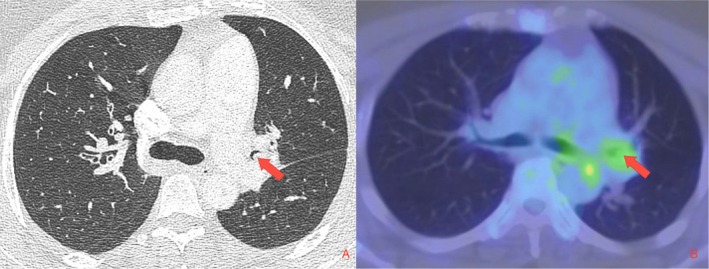

Pulmonary leiomyomas are rare benign tumours of bronchial smooth muscle origin. They can present either in the lung parenchyma or tracheobronchial tree, with 45% being located endobronchially. Endobronchial leiomyomas typically present with airways symptoms such as dyspnoea, cough, and obstructive pneumonia. Traditionally, endobronchial leiomyomas were managed surgically with lobectomy or pneumonectomy but, increasingly, management has shifted to bronchoscopic resection with different endoscopic techniques described in the case report literature. Most reports include outcomes ranging from 3 to 6 months following bronchoscopic resection. We present a case of a 40-year-old female with a left upper lobe (LUL) leiomyoma who presented with complete LUL collapse consolidation. Bronchoscopic resection was performed using a combination of diathermy snare, cryo-recanalisation, and argon plasma coagulation (APC) which resulted in excellent restoration of the LUL patency. Annual bronchoscopy surveillance over 7 years confirmed durability of the procedure with no recurrence detected.